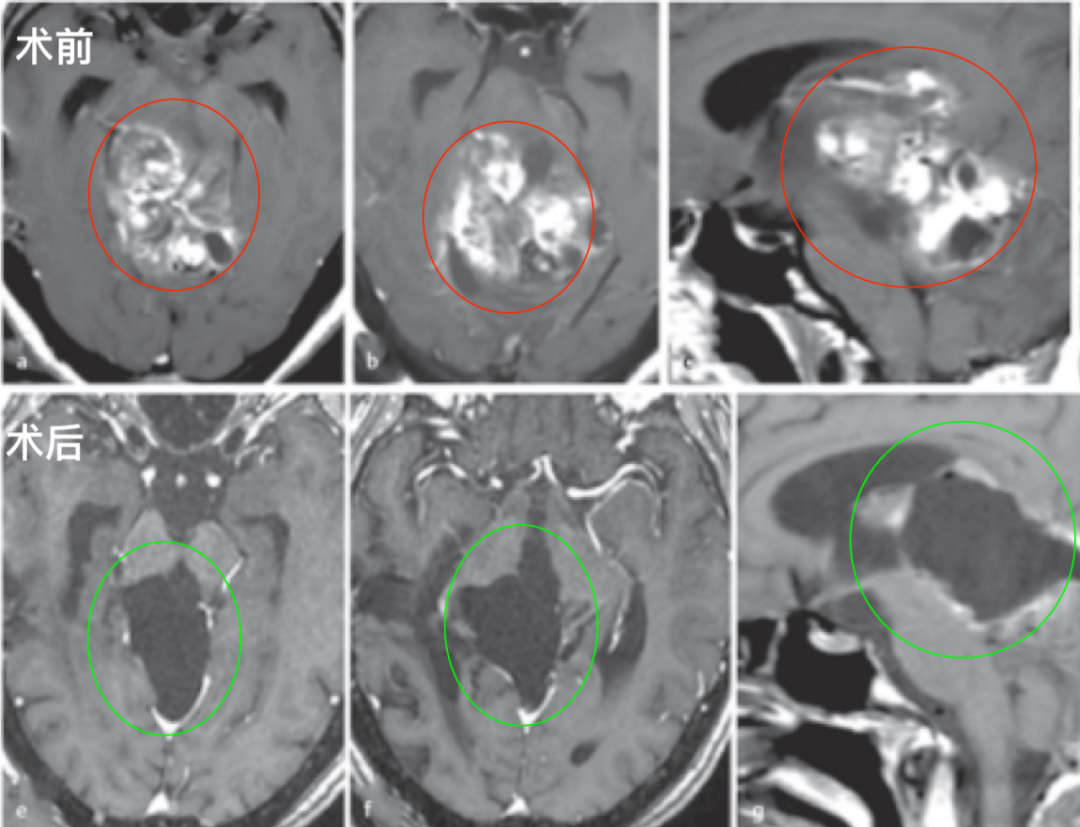

经检查确诊男孩患有海绵状血管瘤。虽然该病变属良性性质,但可能引发脑干出血,导致瘫痪、功能永久性损伤甚至死亡等严重并发症。然而病情恶化速度超出预期。...

更新时间:2025-12-02 09:11:36

淼淼父母观察到孩子出现一系列异常表现:临床表现为嘴角歪斜、流口水及斜视等症状,这些均为既往未曾出现的体征。经医院系统检查,确诊为颅内巨大海绵状血管瘤,该病灶已引发脑干出血。...

更新时间:2025-12-01 10:52:50